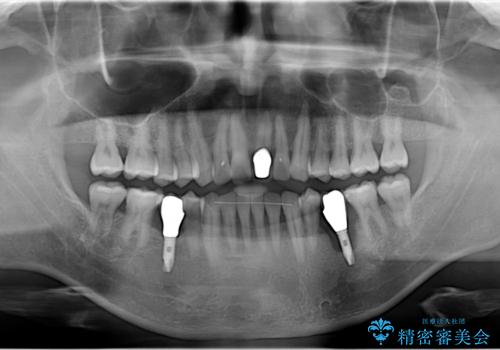

- 20年振りの来院で下顎左右5番にインプラント入れていた患者様です。

右下5番のインプラントは問題ありませんでしたが、左下5番のインプラントがインストール周囲炎に罹患している状態でした。

インプラントを抜去後、再びインプラントで治療を行いました。

20年以上振りのご来院でした。